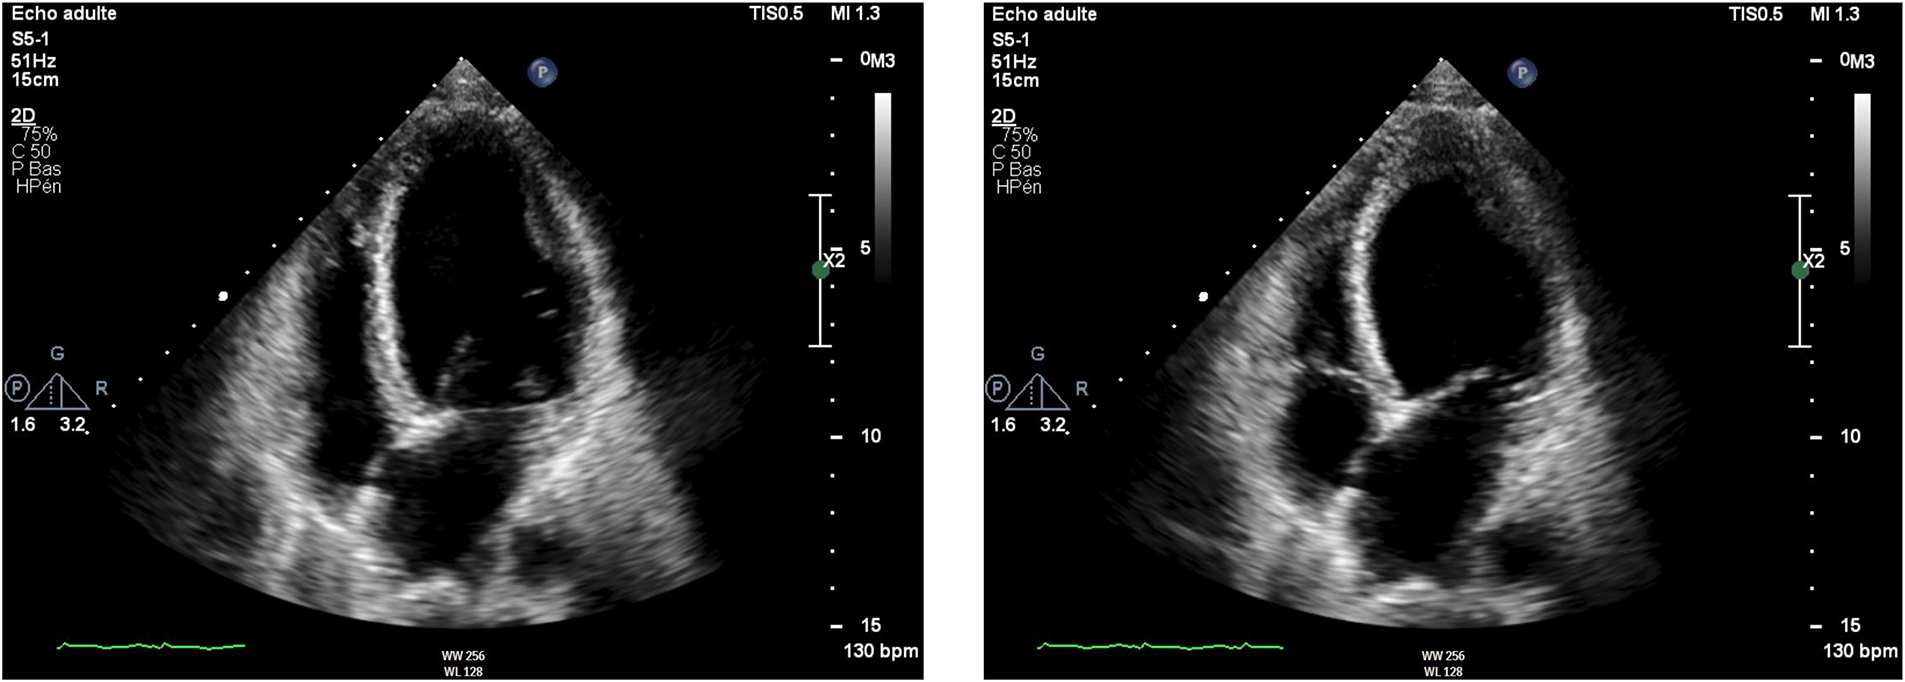

Initial evaluation with TTE was suggestive of cardiogenic shock with an estimated LVEF of 15 to 20%. Because of the severity of the situation and the young age of the patient, a transfer to the academic tertiary care hospital was decided. Upon arrival, a total-body-CT was performed to rule out intracranial bleeding, pulmonary embolism, and an infectious or neoplastic process. TTE was repeated on day one and was relevant for severe LV dysfunction (LVEF of 24%), and findings suggestive of reverse TTS, with basal and mid-ventricular segments akinesia and a spared apical contractility (Figure 3: Transthoracic echocardiography performed at day one, showing a severely reduced left ventricular ejection fraction (24%) with basal and midventricular segments akinesia, and preserved apical contraction. There was no significant valvulopathy and right ventricular function was normal. Panel A: Diastole, Panel B: Systole). In the absence of localized wall motion abnormalities matching the territory of a coronary artery, and considering the young age of the patient, with no known personal or familial cardiovascular risk factors, coronary angiography was not performed as the probability of coronary artery disease was considered very low. Hs troponin T levels rose to a peak of 1,894 ng/L on day one, with a subsequent decrease. The clinical situation rapidly improved and the patient was extubated on day two. On day four, a cardiac MRI was performed, showing an improvement of the LVEF to 46%. Horizontal long-axis, color-coded images from T2-mapping revealed hyperintensity in the basal and mid-ventricular segments of the left ventricle that confirmed the presence of regional circumferential myocardial oedema (Figure 4: cardiac MRI images from T2-mapping revealing myocardial oedema in four, three and two-chamber views), as well as the absence of late gadolinium enhancement (supporting the idea that there was no irreversible myocardial injury) (16). Based on these observations, two diagnostic hypotheses were put forward: reverse TTS or an inflammatory cardiomyopathy. However, regarding the latter hypothesis, the Lake Louise criteria were not fulfilled (17), reason why reverse TTS was considered the most likely diagnosis, despite the patient having an InterTak Diagnostic Score of only 46 (25 points for female gender, 12 points for no ST-segment depression and 9 points for the acute neurological trigger), meaning a 9.8% probability of TTS (1).

Figure 3

Transthoracic echocardiography performed at day one, showing a severely reduced left ventricular ejection fraction (24%) with basal and midventricular segments akinesia, and preserved apical contraction. There was no significant valvulopathy and right ventricular function was normal. A: Diastole, B: Systole.